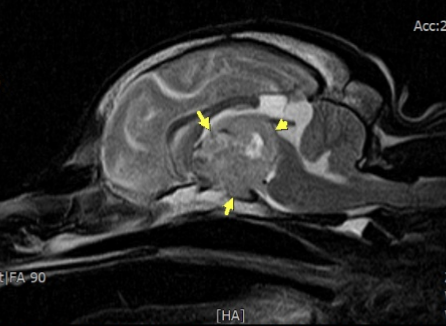

뇌하수체 종양은 MRI 촬영이 가장 정확한 진단법으로, 종양의 크기·위치·주변 조직 침습 여부까지 평가할 수 있습니다.

환자는 정확한 진단을 위해 MRI 촬영하였고 뇌하수체 종양으로 진단되었으며, 소뇌 탈출까지 동반된 상태였습니다.